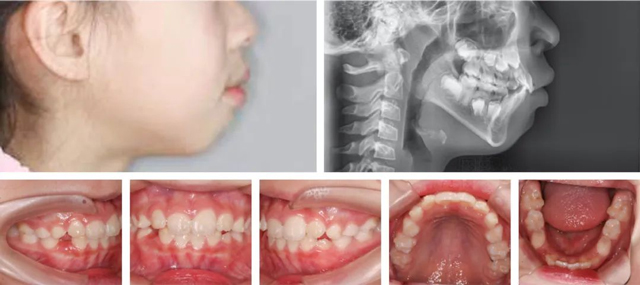

经过详细检查,并结合数字化口扫、CBCT和头颅侧位片,医生发现朵朵侧貌上唇前突,闭唇时颏肌和唇肌紧张,闭嘴困难,出现了“腺样体面容”:上牙前突、唇外翻、唇形肥厚、下巴收紧等。

矫正前

结合口内牙齿、面型、牙片综合评估,孙叡医生制定了一份详尽的矫正方案:扩弓排齐牙齿,解除侧切牙的拥挤状况,给后续恒牙萌出留出位置,并适量内收上颌前牙改善外观。同时还要进行唇肌功能训练,以改善口呼吸的习惯。